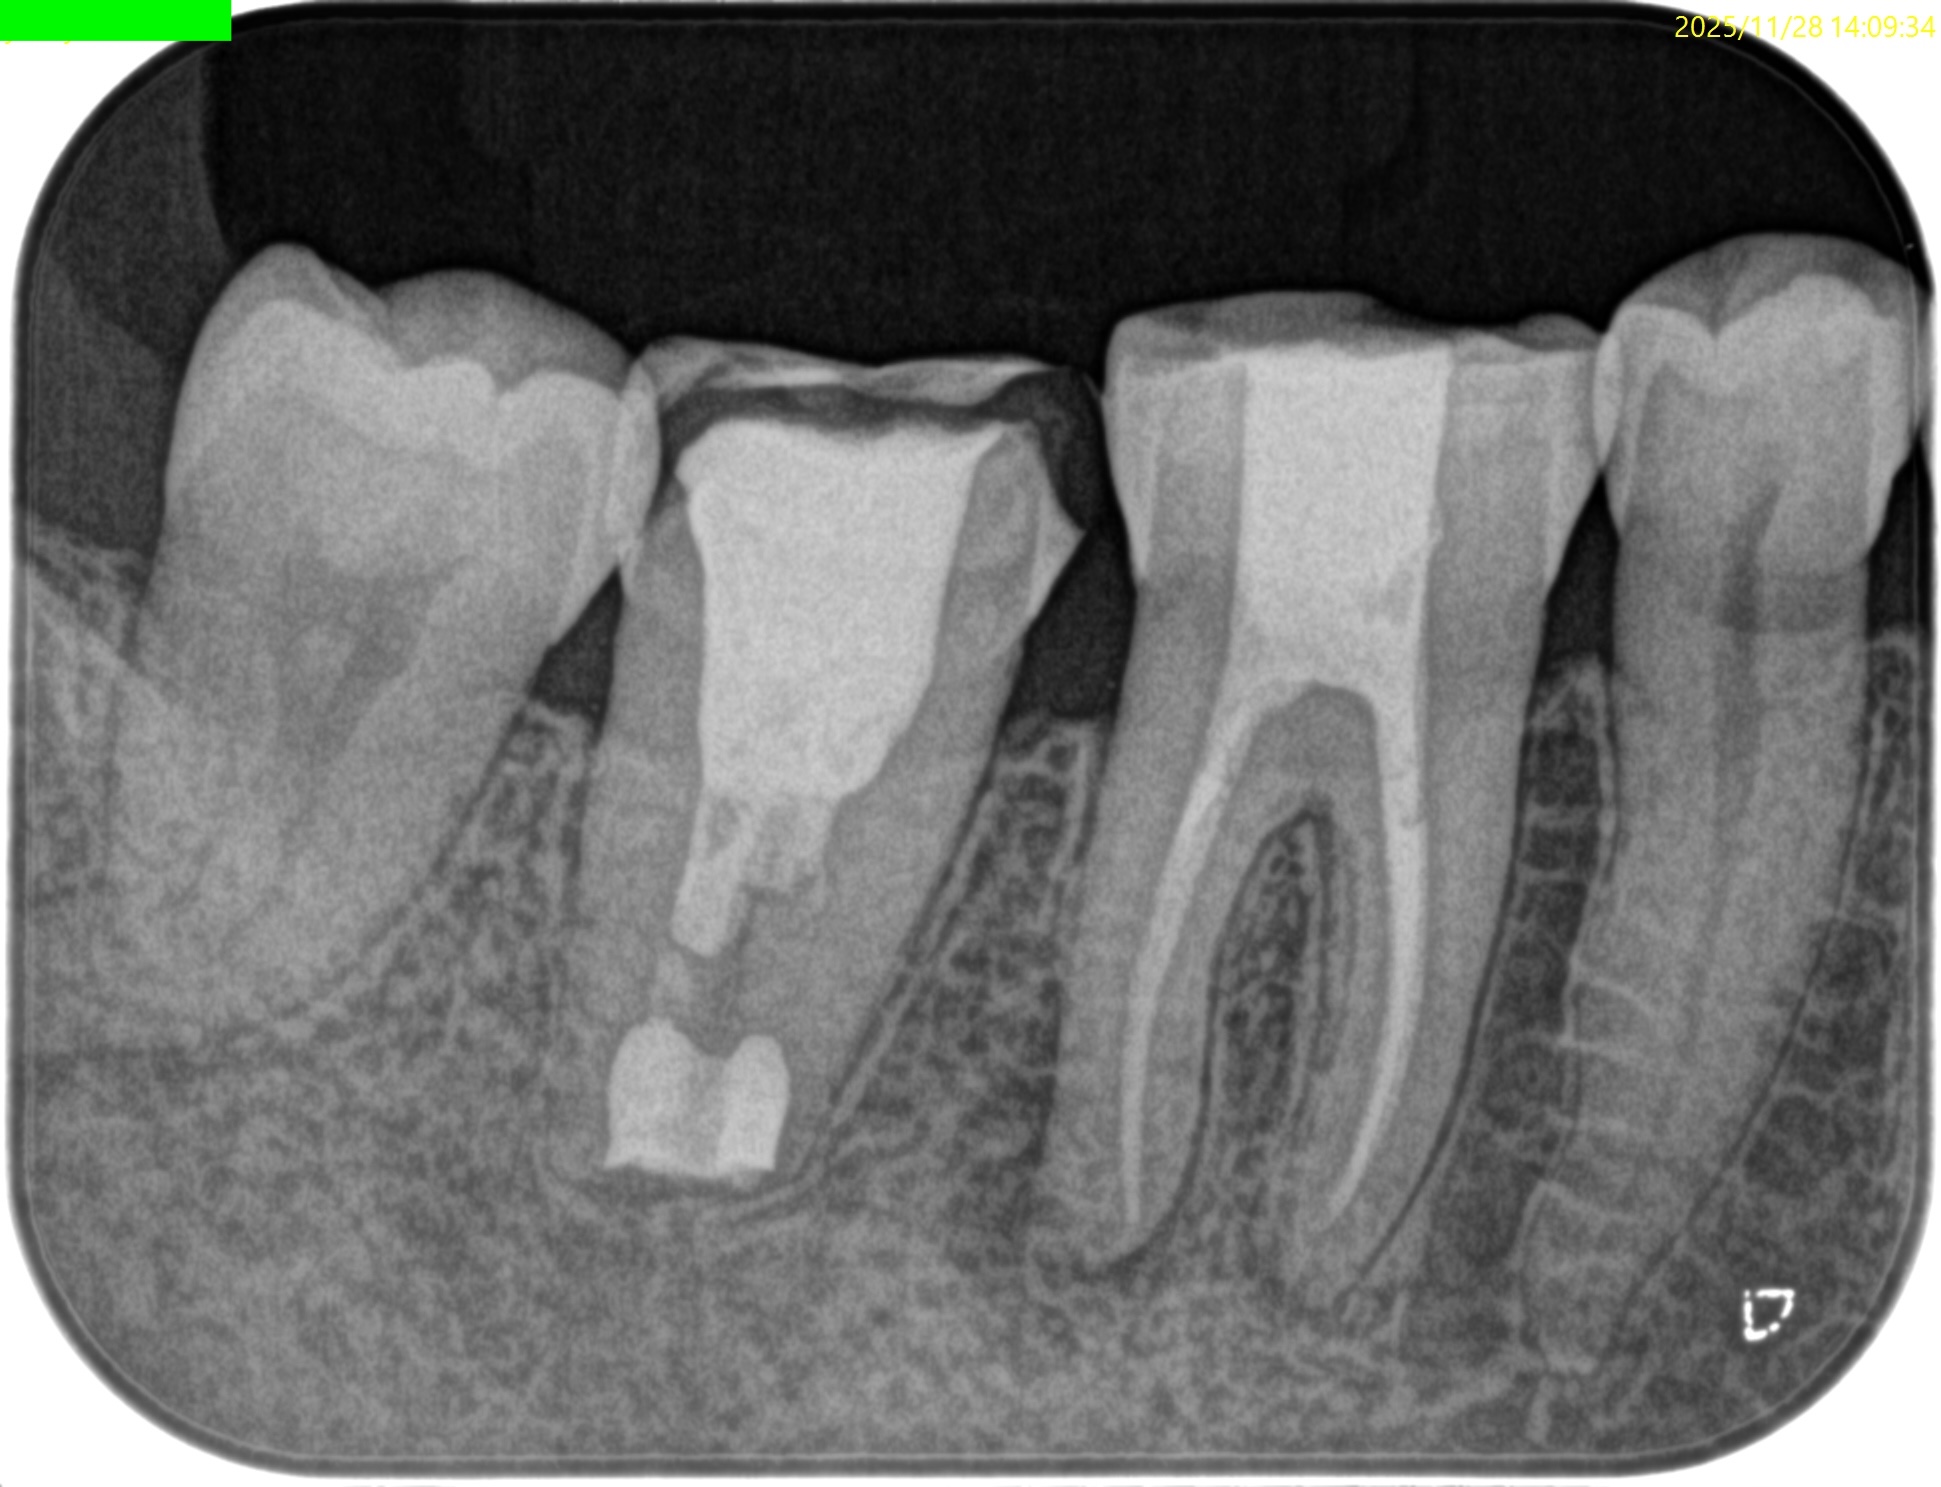

#31 Intentional Replantation 1yr recall(2025.11.28)

初診時と比較した。

劇的に治癒していることがわかる。